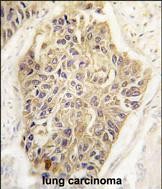

- Formalin-fixed and paraffin-embedded human lung carcinoma tissue reacted with MAGEA1 Antibody (Center) (Cat.#P30091), which was peroxidase-conjugated to the secondary antibody, followed by DAB staining. This data demonstrates the use of this antibody for immunohistochemistry; clinical relevance has not been evaluated.